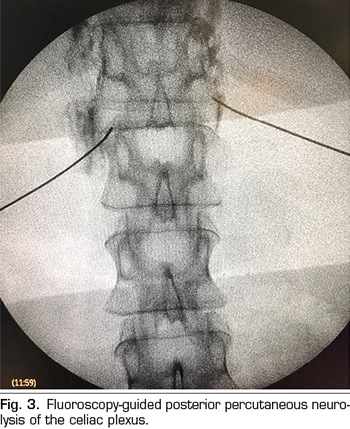

Transcrural approach: the most commonly used for the blockage of the celiac plexus (Figure 3). The patient is placed in prone position, identifying the vertebral body L1 and advancing a needle on each side, approximately 7.5 cm from the midline, until it crosses the diaphragmatic crura and blocks the plexus.

Percutaneous celiac plexus neurolysis consists in the destruction of the fibers composing the celiac plexus by injecting a neurolytic agent, the use of alcohol is preferred due to its lower affinity for blood vessels compared to phenol. The most commonly used classical approach is the bilateral transcrural posterior, guided by fluoroscopy or CT.